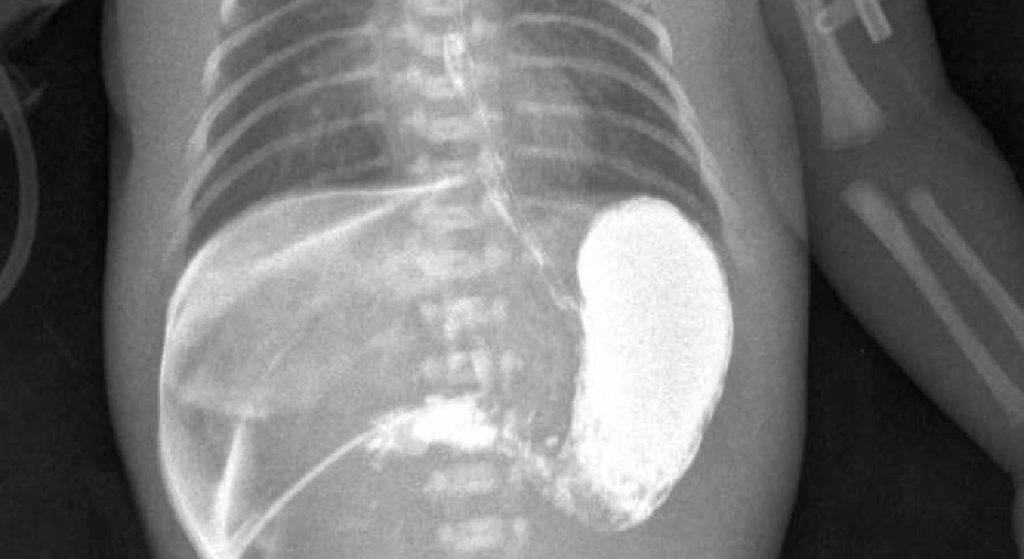

Также дополнительным методом исследования является рентгеконтрастирование – пассаж бария по ЖКТ. Хотя рентгенологическое исследование несёт лучевую нагрузку, оно является информативным и позволяет точно определить проходимость привратника. Ребёнку через рот даётся около 30 мл контрастного вещества (5% взвеси бария в грудном молоке или 5% растворе глюкозы). Обзорная рентгенография брюшной полости выполняется через час и четыре часа, после дачи контраста. При пилоростенозе на снимке будет определяться большой газовый пузырь желудка с одним уровнем жидкости. Эвакуация контраста из желудка в двенадцатиперстную кишку замедлена. После проведения обследования желудок необходимо опорожнить, чтобы при последующей рвоте предотвратить аспирацию бария.